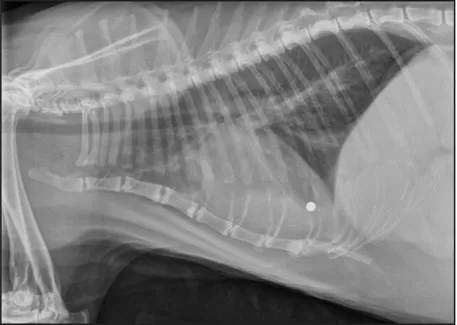

CASE 1.1 A 7-year-old neutered male Labrador Retriever who was hit by a car. You obtain these thoracic radiographs: Figs. 1.1a, b, left and right lateral projections, respectively; Figs. 1.1c, d, ventrodorsal and dorsoventral projections, respectively.

1.1d